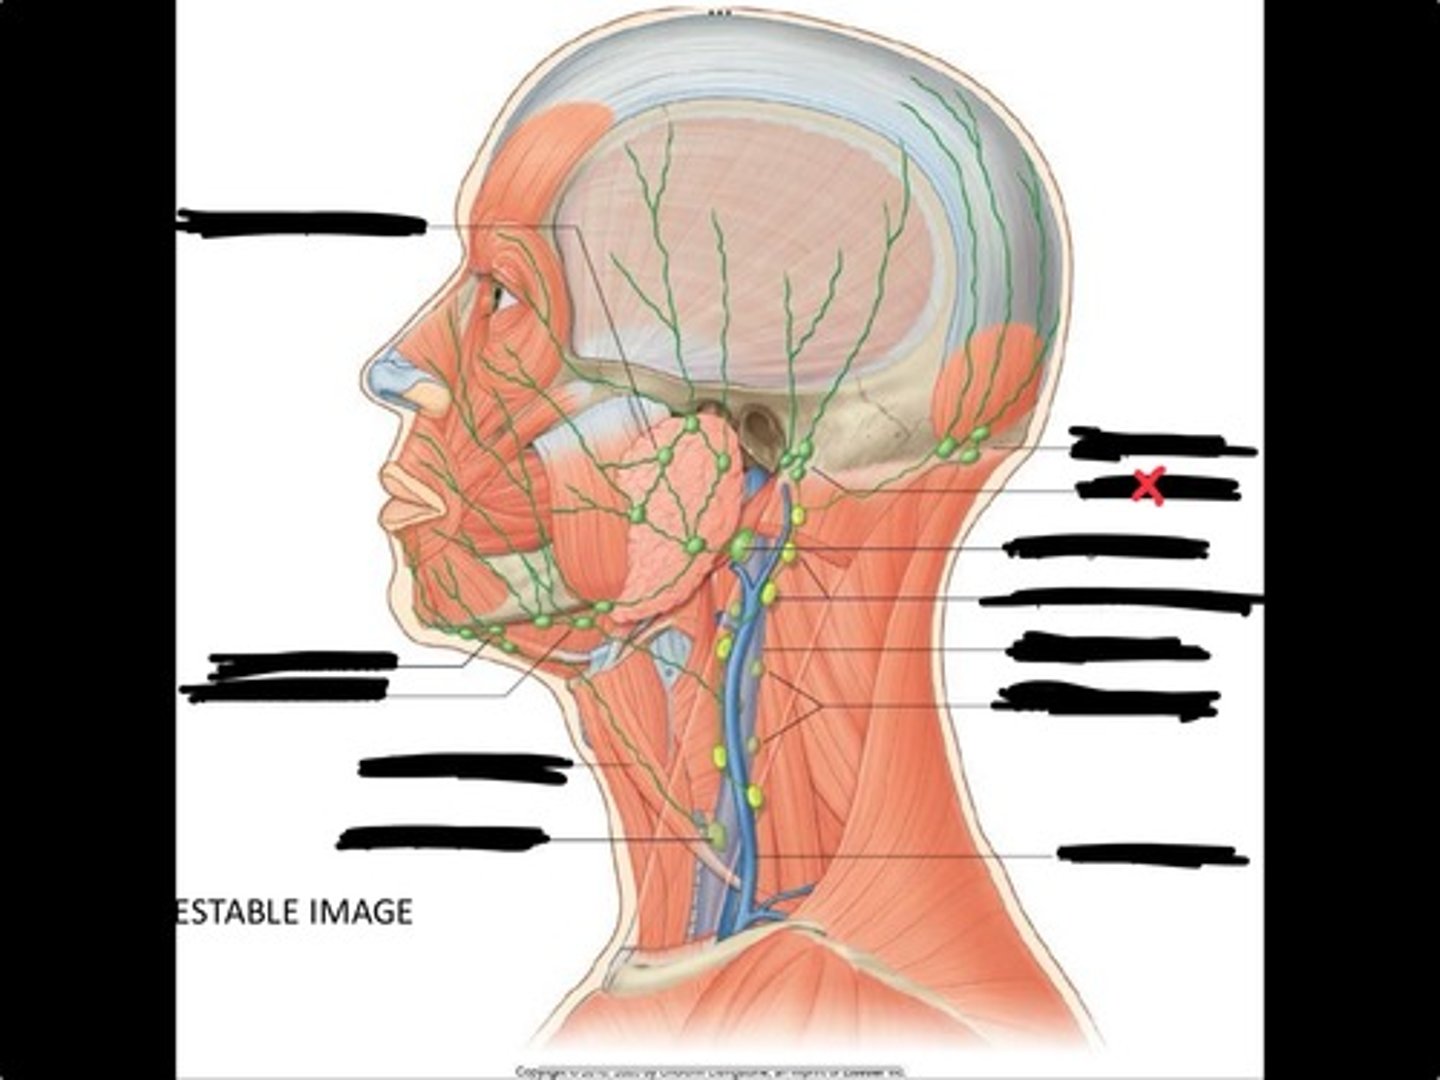

Jugulo-omohyoid node

Submandibular nodes

Submental nodes

Pre-articular/parotid nodes

Occipital nodes

Mastoid nodes

Jugulodigastric nodes

Superficial cervical nodes

Internal jugular vein

Deep cervical nodes

External jugular vein